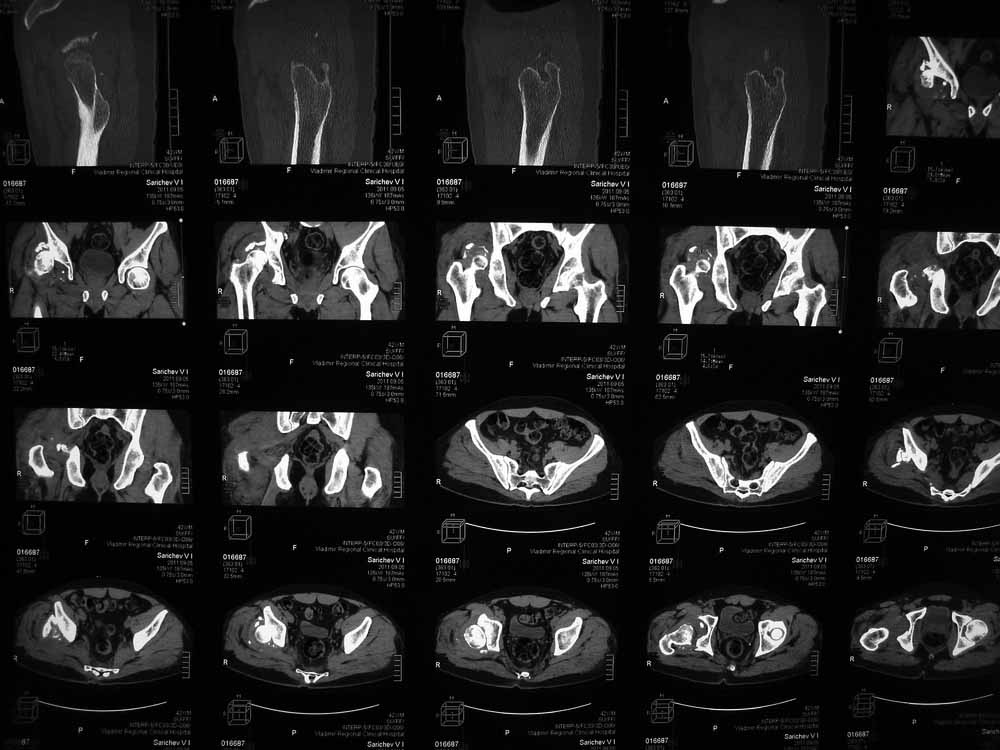

42 года, майор запаса. Травма от 20.06 - ДТП. Лечился в гражданском ЛПУ. Вывих бедра диагностирован только 4 недели спустя. "Тянулся", неоднократно - попытки закрытой репозиции. Попытка открытой репозиции - без результата. Потом опять пытались закрыто, сказали, что вправили, тянулся. После снятия ССВ - опять вывих. Поступил к нам. Сейчас - СРБ больше 10, в ОАК - воспаление. Местно - головка кзади и кверху, укорочение 7, голова подвижна. Отек, незначительная боль в в/3 бедра. Пассивно из наружной ротации выводится, активных движений в ноге нет. Рубец по наружной поверхности верхней трети бедра, без воспаления. Каким образом выполнялось открытое вправление - данных нет. Окончательно снят с вытяжения 2 недели назад.

Структуру головки не очень хорошо видно, есть перелом нижнего отдела головки БК, сломанный задний край небольшой. Срок после травмы 4 недели, молодой возраст. Есть смысл синтезировать ВВ, а дальше посмотреть. Будут проблемы - легче будет протез ставить, ну а если лет 8-10 сустав поработает, то и это хорошо. Если вы уж решили делать протезирование, не мудрите, вполне можно обойтись стандартной вертлужной впадиной с укреплением ее винтами.

Вот еще сканы.

В этой ситуации предпочел бы эндопротез, шансы на жизнеспособность головки в таком сроке вывиха исчезающе малы, попытка синтезировать задний край в этих же сроках (ретракция мышц, рубцы) скорее всего приведут к его девитализации с последующим аваскулярным некрозом. Выбор вертлужного компонента проще планировать после 3D, скорее всего можно будет обойтись стандартными предложением, возможно, с котилопластикой.